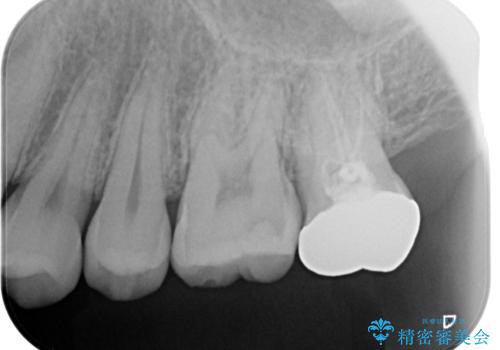

過去に根の治療もされている歯だが土台が粗造なため根の治療からやり直しを行いゴールドクラウンにて治療を行いました。

- PGAクラウン・仮歯 13.2万円 精密根管治療・コア 16.5万円 e-maxインレー 7.7万円費用は治療当時の料金となります

適合の良い被せ物が入りました。

ゴールドの被せ物は適合がよく虫歯の再発のリスクが低くなります。

また根の治療を行う時はラバーダムを行い治療しています。